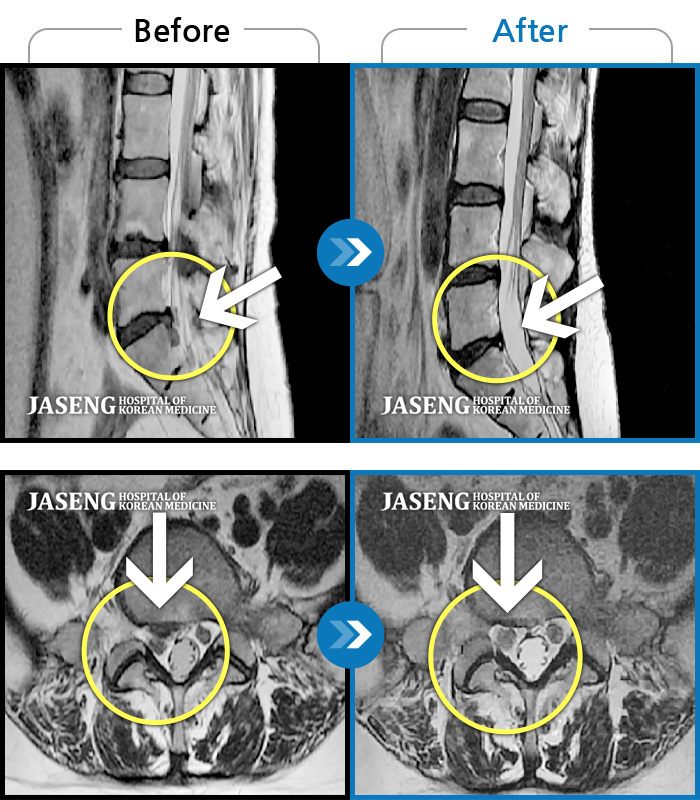

허리디스크

도움받은 사례

해운대 · 김상돈 원장

하지 저림과 통증이 개선되어서 일상생활이 너무 즐겁습니다.

촬영시기

2023.09.18 ~ 2025.01.27

2025.02.05

조회수 16,646